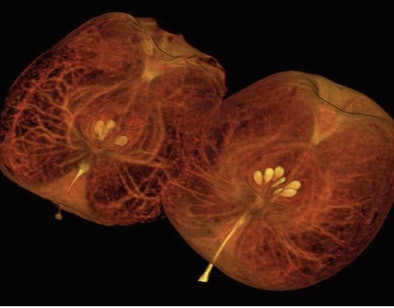

During a live demonstration that included scanning acorn squashes and watermelons for the benefit of a reporter, the staff compared images from CT750 HD side-by-side with the older GE model, revealing finer resolution of internal structures in the former.

Then again, produce doesn't move around much. A beating heart does, and because the CT750 HD retains LightSpeed VCT's 64-slice configuration, its motion-freezing capabilities are essentially unchanged from those of the current 64-slice LightSpeed scanner, according to GE.